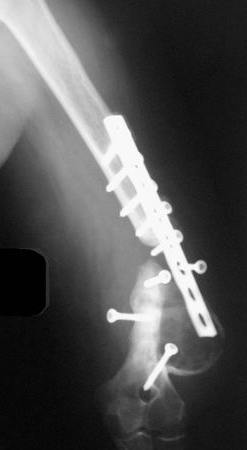

На примере два случая, извиняюсь за качество снимков, снимки и случаи из бывшего союза.

Первая больная с "успехом" была прооперирована 6 раз различными методами открытого и закрытого

остеосинтеза, включая то, что в Кисловодске заезжим австралийским "кудесником" на ложный сустав уложена скорлупа от страусиновых яиц. Последняя операция одиноким локинг плейт в одной из клиник.

Через год по поводу тех же проблем сделали ревизию, оригинальную пластину оставили как есть, только укрепили добавлением еще одной пластины и сделали костную пластику.

Через два месяца увидели признаки консолидации.